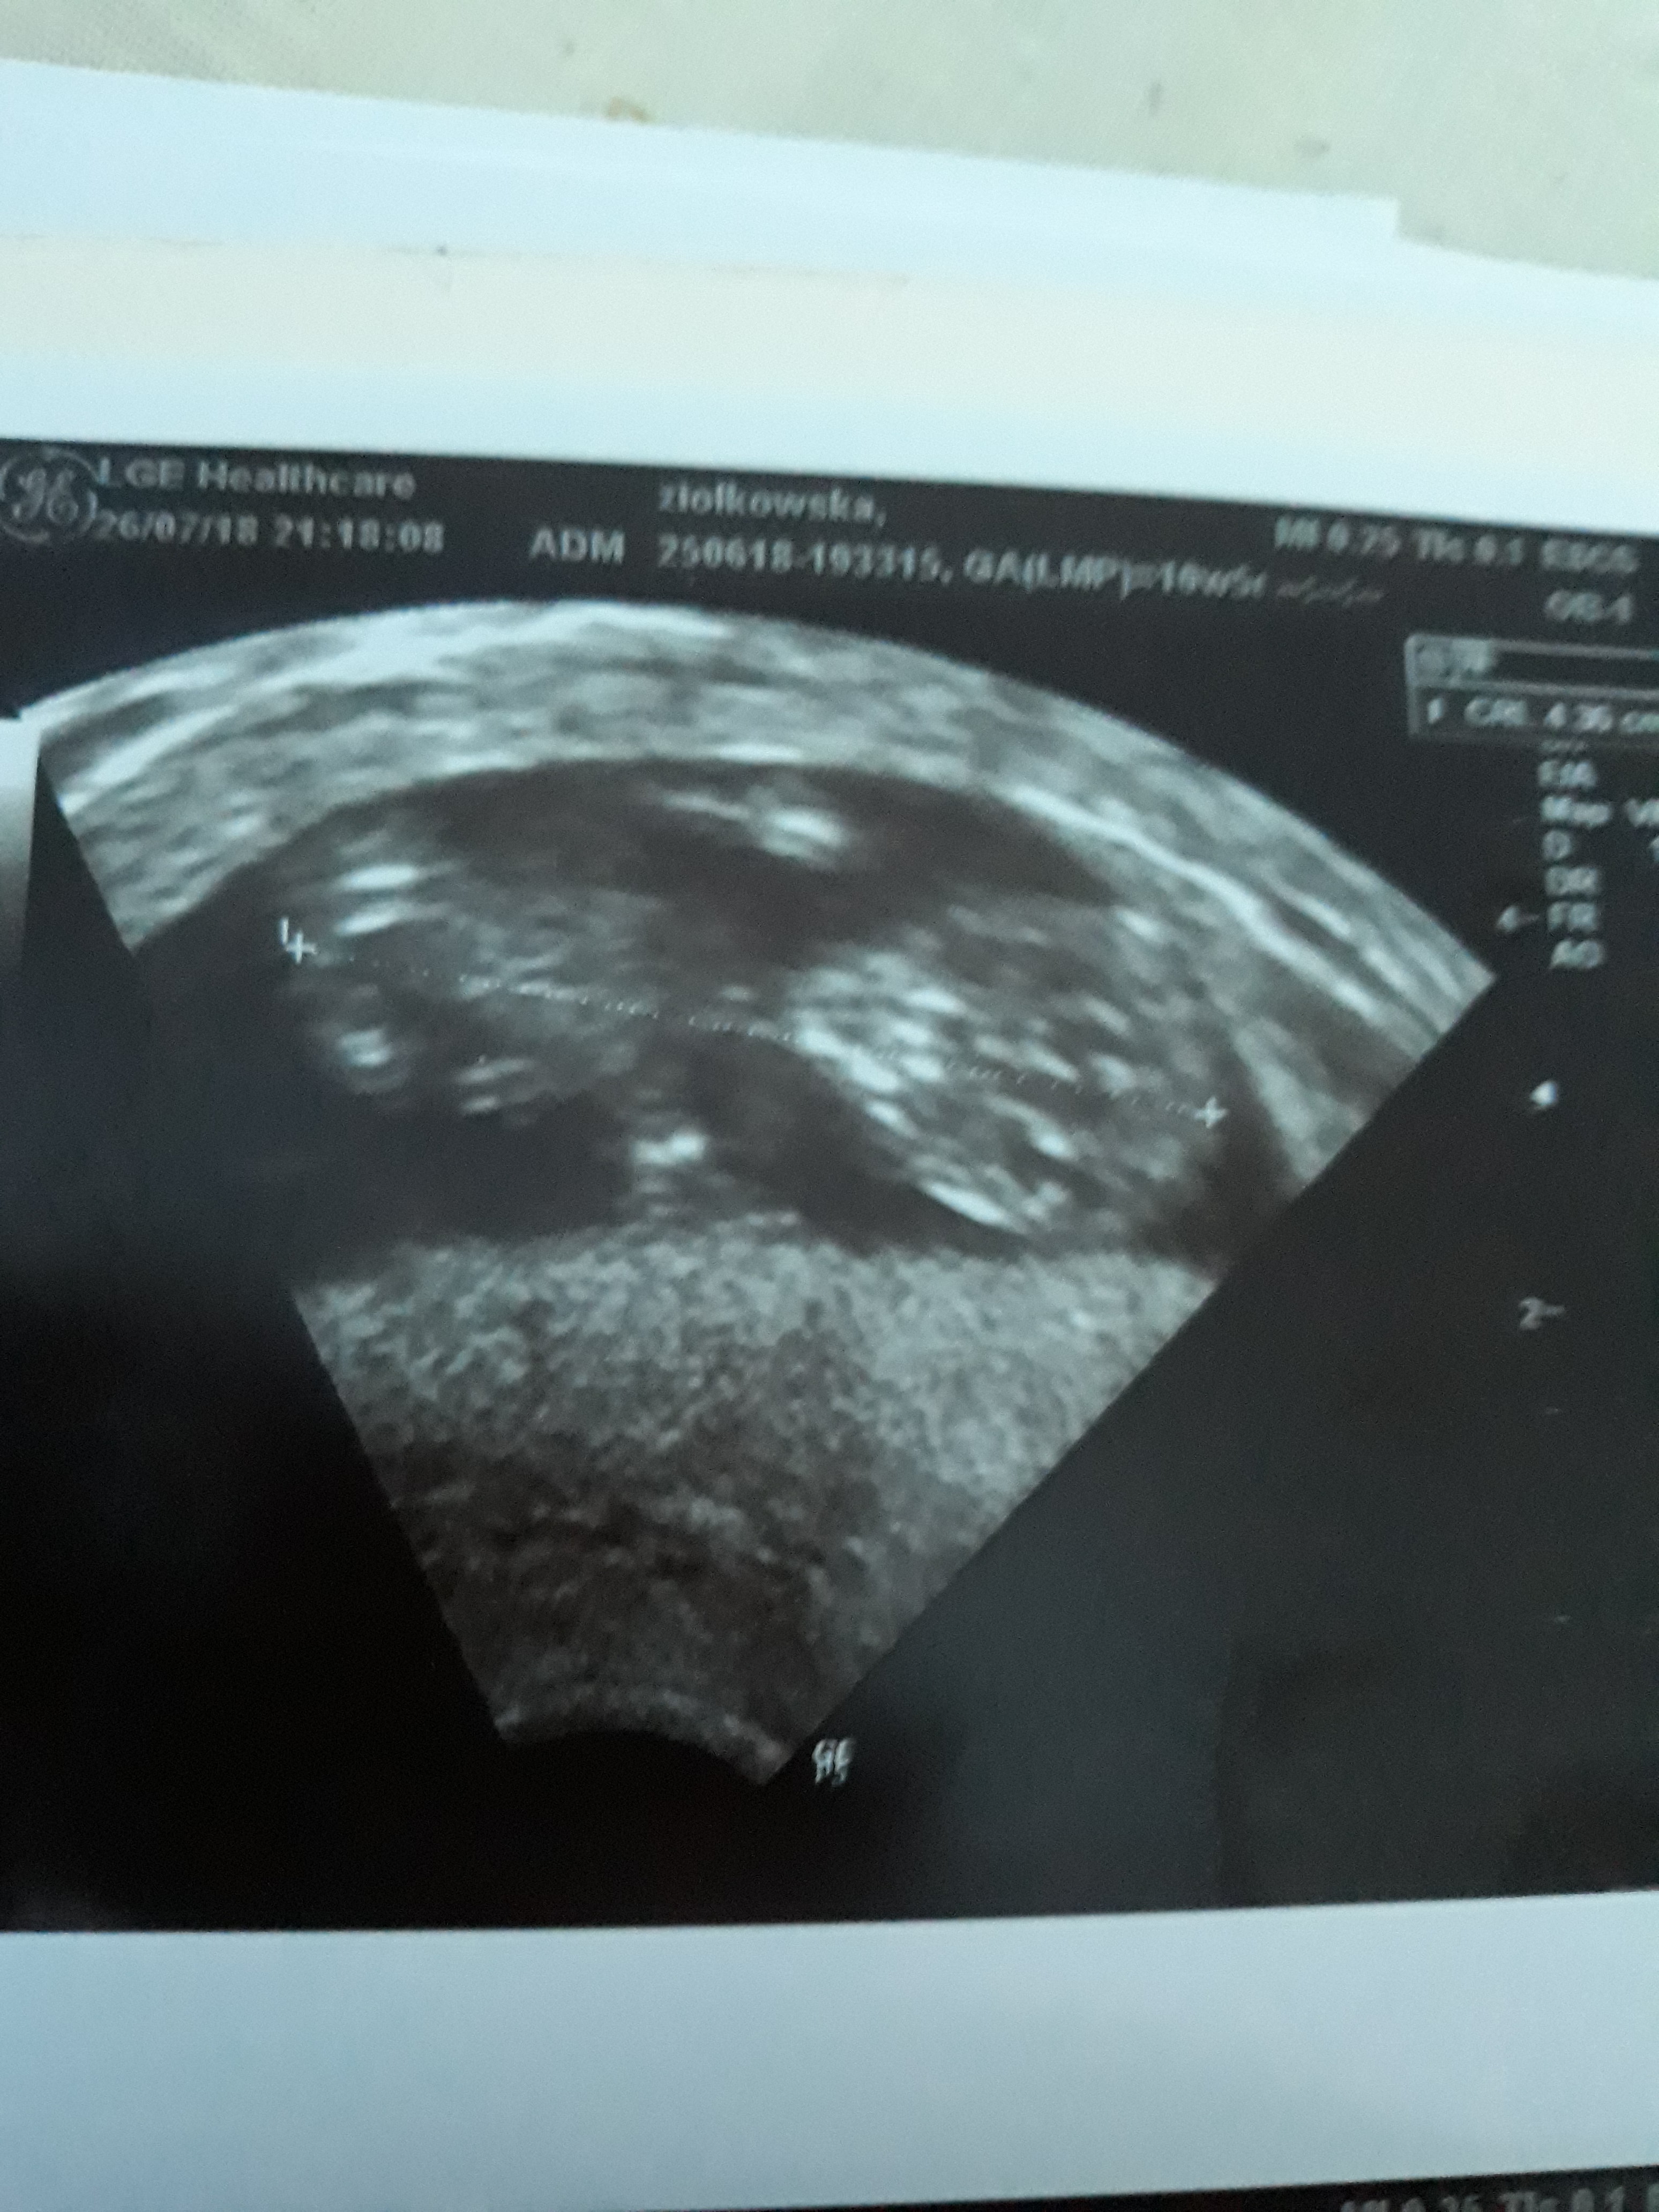

Super Gosiu [emoji9][emoji9] 4.7cm to juz jest kawal dziecka [emoji4] zdrowka dla Was Kochana [emoji173][emoji173]Z naszym bejbikiem wszystko ok [emoji173][emoji173] pieknie rosnie ma juz 4.7cm pieknie pykajace serduszko nozki raczki i dalej przypomina alienaodrazu widac ze bedzie piekna Oliwia :* cudzie trwaj [emoji173][emoji173]

Krwiak zmnieszyl sie do 0.7 cm na 1.4 cm wszedzie czysto dalej prowadzimy oszczedny tryb zycia ale mozemy juz wychodzic na spacery i nawet jezioro dozwolone